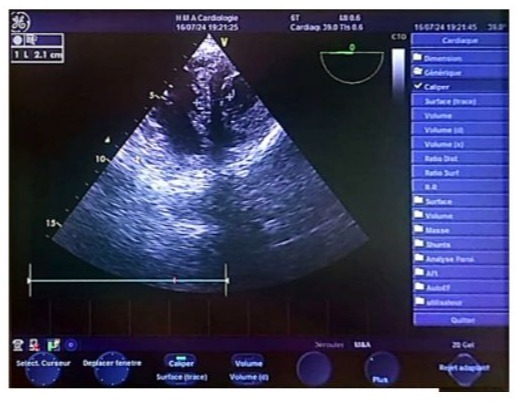

We report the case of a 70-year-old female patient with a history of poorly controlled arterial hypertension, presenting with two coexisting conditions that required either a two-step approach or simultaneous management, involving a thyroidectomy followed by cardiac surgery under cardiopulmonary bypass (CPB). In our case, a simultaneous approach was chosen following a multidisciplinary consultation. With a medical history of poorly controlled arterial hypertension, a multinodular plunging goiter in hyperthyroidism treated with carbimazole 10 mg/day, and atrial fibrillation associated to severe aortic valve stenosis managed with acenocoumarin 4 mg (¼ tablet/day) and bisoprolol 2.5 mg/day, the patient presented with a progressively worsening condition. The onset of her symptom’s dates back to five months prior, marked by a brief episode of syncope, prompting an emergency consultation. Initial evaluation revealed tachycardia due to atrial fibrillation on a background of severe aortic valve stenosis. She was placed on symptomatic treatment. The course of her illness was characterized by a worsening baseline dyspnea, progressing from NYHA class II to class III, accompanied by exertional palpitations without chest pain. The patient was referred to the ENT consultation for progressively worsening dyspnea, associated with orthopnea and a massive goiter, and cardiology consultation for the evaluation of her heart disease. During her recent assessment she also reported reduced exercise tolerance and occasional dizziness with neck symptoms, including subclavicular pain and swallowing limitations. Clinical examination revealed a large goiter deforming the neck, visible on inspection, with signs of tracheal compression. Cardiac auscultation identified an intense systolic ejection murmur at the aortic focus radiating to the carotids, with no signs of right-sided heart failure or peripheral edema. Thyroid ultrasound showed a multinodular goiter containing hypoechoic cystic areas and calcifications, with a plunging thoracic component compressing cervical and superior mediastinal structures. A cervical-thoracic CT scan, with and without contrast injection, confirmed the plunging nature of the goiter. It extended into the anterior mediastinum, displacing the trachea and major vessels without evidence of invasion. The scan revealed a multinodular goiter characterized by generalized thyroid gland enlargement, predominantly affecting the left lobe, with an irregular, lobulated contour. The goiter is characterized by heterogeneity, macrocalcifications, and uneven enhancement, marking hypodense necrotic and/or cystic fluid-filled areas. The large goiter measures 12.13 x 9.06 x 6.63 cm in the left lobe, 10.5 x 6 x 5.36 cm in the right lobe, and 5 cm in the isthmus. It extends upwards to the submandibular spaces and laterally towards the anterior and posterior spinal spaces, particularly on the left side. The jugulo-carotid vascular axes are displaced laterally and posteriorly, but remain unobstructed. The goiter extends downward into the superior level of the anterior mediastinum, filling the prevascular space and pushing vascular structures posteriorly. It reaches the level of the superior border of the aortic arch, coming into contact with the supra-aortic trunks, exerting a mass effect, but without invasion or obstruction. The upper aerodigestive pathways are unobstructed and symmetrical, although there is posterior and rightward displacement at the larynx and trachea level, without narrowing or impact on their lumen, which remains patent and of normal size. (Figure 1) Transthoracic echocardiography revealed severe degenerative aortic stenosis with high pulmonary arterial hypertension for age (PASP through tricuspid regurgitation at 55 mmHg). The left ventricle was non-dilated, hypertrophied with an indexed mass of 107.11 g/m² (eccentric remodeling), end-diastolic diameter (EDD) at 44 mm, end-systolic diameter (ESD) at 28 mm, and preserved systolic function with an ejection fraction (EF) of 55% (biplane Simpson method). (Figure 2)

Figure 2: Real-time echocardiographic image showing a non-dilated, hypertrophied left ventricle with an interventricular septum measuring 0.9 cm in diastole and 1.2 cm in systole. The indexed left ventricular mass was 107.11 g/m², indicating eccentric remodeling. The left ventricular end-diastolic diameter (EDD) measured 44 mm, the end-systolic diameter (ESD) measured 28 mm, and systolic function was preserved with an ejection fraction (EF) of 66% (Teichholz method). The shortening fraction was within the normal range at 36%.